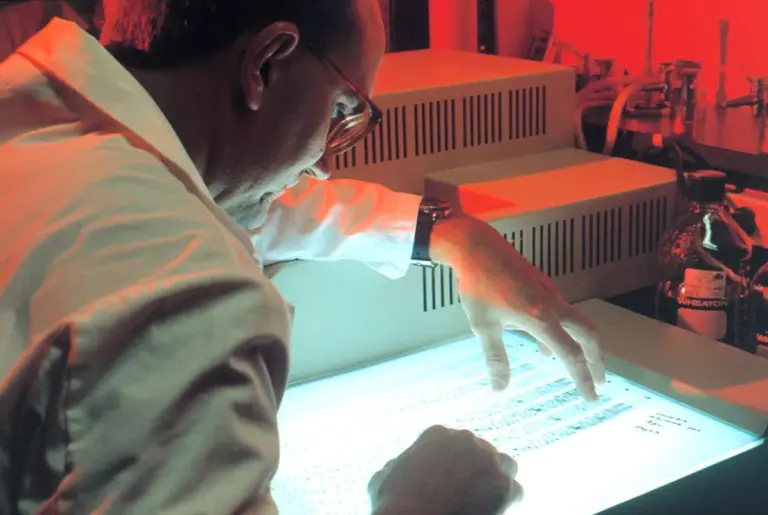

Researchers have made a groundbreaking discovery of giant squid traces in Western Australia using eDNA techniques. This...

A suspected hantavirus outbreak aboard a Dutch cruise ship has resulted in three deaths and additional cases,...

A hantavirus outbreak on the MV Hondius has resulted in three deaths and raised alarms about the...